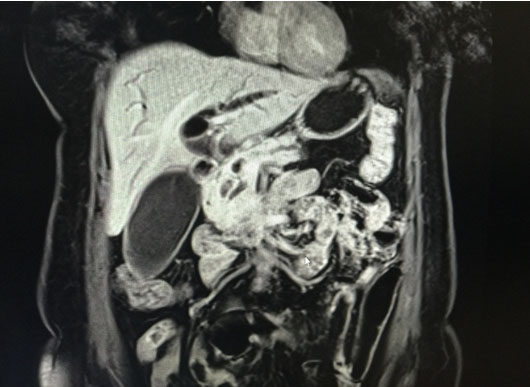

A magnetic resonance imaging (MRI) with magnetic resonance cholangiopancreatography (MRCP) revealed intra and extrahepatic biliary and pancreatic ductal dilatation, with gallbladder hydrops secondary to an obstructing lesion involving the distal CBD and pancreatic duct. The CBD was 1.7 cm with no obstructing calculus. There was a poorly defined heterogeneously enhancing soft tissue mass involving pancreatic head and uncinate process measuring 3.5 × 3.5 × 2.0 cm, which encases and obstructs the distal CBD and pancreatic duct, and abuts the duodenal wall at D2–D3 segment. Few nonspecific subcentimeter peripancreatic, aortocaval, and para-aortic lymph nodes, measuring up to 7 mm in short axis diameter, were seen (Figure 1 and Figure 2).

Figure 2: MRI showing gallbladder hydrops, secondary to an obstructing lesion involving the distal CBD and pancreatic duct.